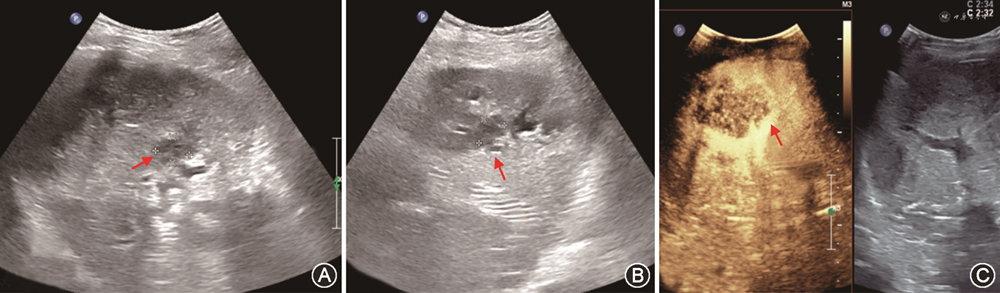

(4)脾动脉窃血综合征(splenic artery steal syndrome,SASS):SASS是指扩张的脾动脉从肝动脉处窃取或抢夺了血流,使得肝动脉向肝实质内血流灌注减少的一种现象。SASS发生率为3.1%~5.9%,主要发生在具有脾功能亢进、脾动脉相对增宽的肝硬化患者。SASS多发生在移植术后2个月内,是急性HAT重要原因之一。SASS发生时,CDFI在肝内、外动脉测及低速高阻血流(PSV<35 cm/s,RI>0.8),同时可见脾肿大、脾动脉增宽[66]。超声造影表现为肝动脉延迟出现(肝动脉与门静脉造影剂出现的时间差缩短)、显影暗淡;同时可见门静脉显影明显增强[67, 68](图15)。需注意,超声造影发现肝动脉延迟出现且显影暗淡时,还需排除其他导致移植肝动脉低灌注的原因如肝动脉血管收缩、HAS等,联合应用超声造影及CDFI检查可进行鉴别,流程如图16所示[33,69]。